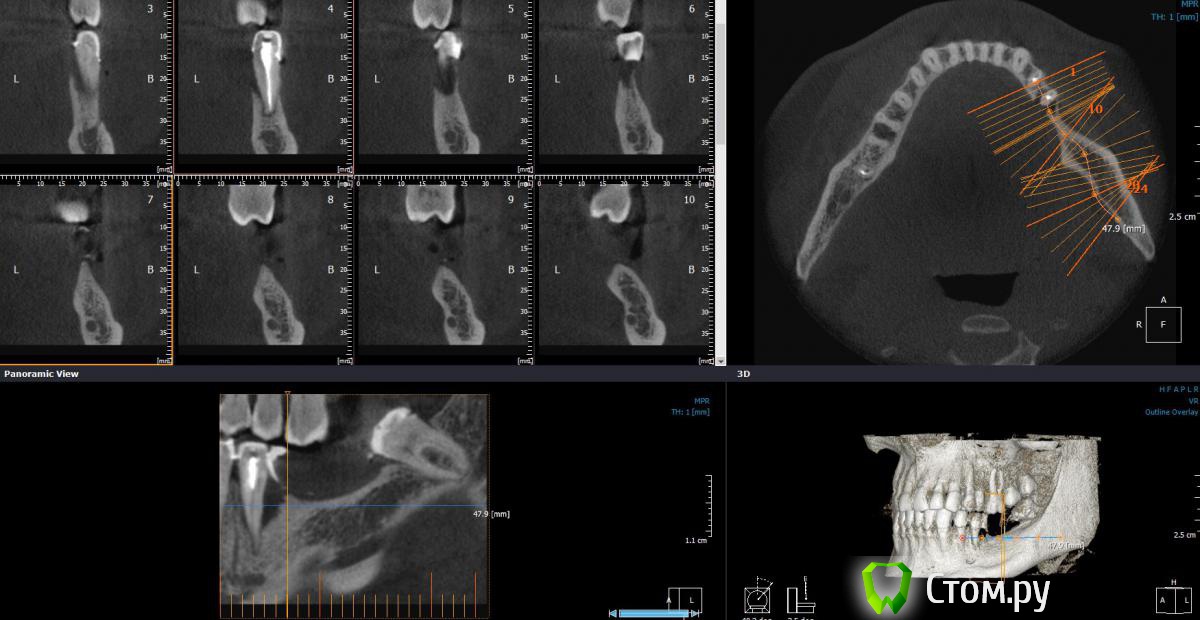

Dantist55 Опубликовано 2 марта, 2014 Автор Поделиться Опубликовано 2 марта, 2014 По-моему все замечательно) будем ждать дальнейшего развития событий. какой графт был?Ауто+ксено(Bio-Oss) - 50/50 Ссылка на комментарий

Dantist55 Опубликовано 2 марта, 2014 Автор Поделиться Опубликовано 2 марта, 2014 Мне очень понравилось.Сколько по времени заняла операция?Расскажите,пожалуйста,как у Вас получился шов щёчно?Где проводился разрез первонвчально?И последнее фото-это сразу после операции или через несколько дней?По времени около 2-х часов. Доступ осуществлялся по Казаньяну. Методику довольно подробно описал SergeyAL . Вот ссылка http://forum.stom.ru/topic/22256-trekhmernaia-kostnaia-plastika/. Последнее фото сразу после операции. 1 Ссылка на комментарий

Dantist55 Опубликовано 2 марта, 2014 Автор Поделиться Опубликовано 2 марта, 2014 А биоосс зачем добавляли? А в общем супер!!!!!Ауто просто не хватило. Ссылка на комментарий

Mane Опубликовано 2 марта, 2014 Поделиться Опубликовано 2 марта, 2014 Хорошо. Но есть несколько но:Если не чисто ауто то нужна мембрана. Иначе возможно врастание надкостницы. Биоосс выбрал бы помельче или этот бы измельчил пресованием. Дальше по ветви выше блендером бы набрали ауто. Запас был. Верхняя крышка тут только ради пробилактики от врастания надкостницы. Если бы была б мембрана - она не нужна. Ждем результаты. 2 Ссылка на комментарий

Dantist55 Опубликовано 4 марта, 2014 Автор Поделиться Опубликовано 4 марта, 2014 Закручивали винты отверткой или наконечником? Торк важен? Через сколько второй этап планируете?Закручивал отверткой, поэтому какой торк не знаю. Но я думаю, что торк в данном случае большой роли не играет. Второй этап планирую через 3 месяца. Ссылка на комментарий

умножающий печаль Опубликовано 6 марта, 2014 Поделиться Опубликовано 6 марта, 2014 Через три месяца рискуете нарваться на подвижность блоков с дальнейшими ... После таких манипуляций я бы ждал 5-6 месяцев. 1 Ссылка на комментарий

АнтонТЛТ Опубликовано 8 марта, 2014 Поделиться Опубликовано 8 марта, 2014 Кури считает,что 3 мес. достаточно....при чистом ауто 3 месяца, если микс то ждать дольше 2 Ссылка на комментарий